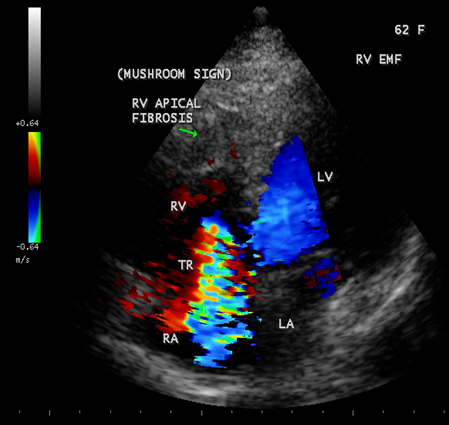

Figure 20: Apical four chamber view showing right ventricular EMF with apical fibrosis and tricuspid regurgitation in a 62-year old female. Fibrotic lesion is characterized by rugose border with a mushroom appearance and thus differentiating from Apical right ventricular hypertrophic cardiomyopathy as shown in Figure-26.

Case 4. Right ventricular endomyocardial fibrosis presented with atrial fibrillation in a 62-year old female as shown in Figures 19 and 20.

When the endocardium is replaced by collagenous fibrosis (consist of collagen deposition and fibroblast proliferation), the final fibrotic stage is reached after several years of disease activity. Fibrotic obliteration of the apices of the affected ventricles is the hallmark of the disorder and fibrosis involving the papillary muscles and chordae tendineae leading to atrioventricular valve distortion and regurgitation. In the left ventricle, the fibrosis extends from the apex to the posterior mitral leaflet, usually sparing the anterior mitral leaflet and outflow tract and cause PML (posterior mitral leaflet) distortion and regurgitation. Like the peculiar geographical distribution, the fibrotic endomyocardial involvement stops short of the ventricular outflow tract like a ridge [17] as shown in Figures 15,29,31,35 and 44. The fibrotic tissue often creates a nidus for thrombus formation, which can be extensive. Atrial thrombi also occur and the right atrium may be aneurysmally dilated. Aneurysmal right atrium with spontaneous echo contrast was detected in a 32- year old male as shown in Figure 36 [18- Figure 3]. In addition, there are fibrosis and granular septation extending into the underlying myocardial tissue and myocyte hypertrophy is common [19]. Fibrotic process causes tethering of leaflets into ventricular walls and may mimic Ebstein’s malformation as shown in Figure 38[20],[21]. Fibrosis increases the stiffness of the heart, resulting restrictive physiology, AV (atrioventricular) valve regurgitation which has been linked to atrial arrhythmias such as atrial fibrillation as shown in Figures 19 and 20 in a 62-year old female. Atrial fibrillation has been reported in more than 30% of patients with EMF. Fibrosis impairs activation patterns of the conduction system and may provide substrate for wave breaks and reentry [22]. Fibrosis reduces conduction velocity and cause conduction abnormalities like junctional rhythms, heart blocks as shown in Figure 21 and 22 in a 75-year old female and atrioventricular conduction delay [23].